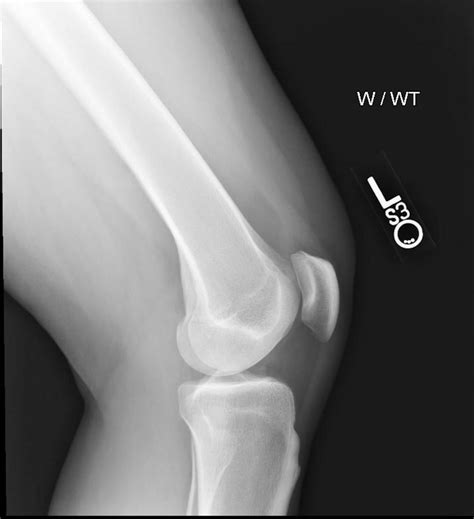

Osgood Schlatter Disease | Treatment, Exercises & Surgery